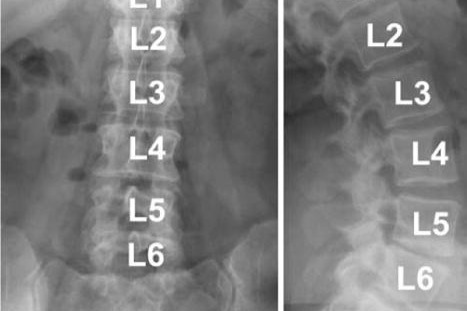

I have a congenital spinal deformity known as LSTV (lumbosacral transitional vertebrae) and in addition to that, I have a 6th lumbar vertebrae. Basically what this means, my lower lumbar vertebrae have fused themselves to my first sacral vertebrae.

Normal lumbar area:

What mine looks like: